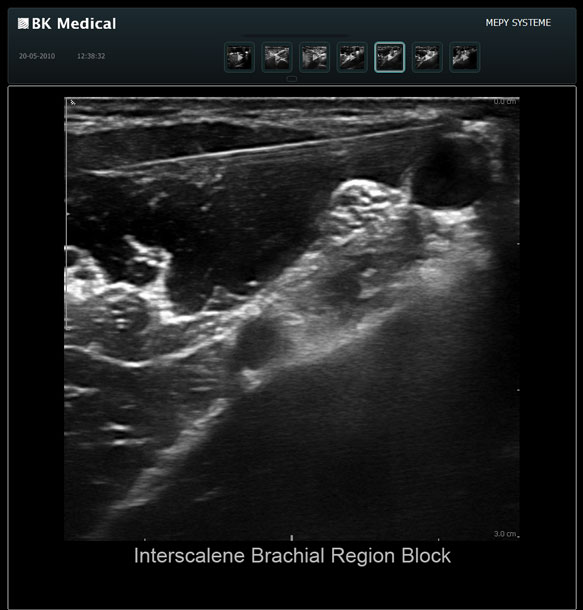

High resolution ultrasound imaging for needle-guided procedures.

The Clearest Image Makes the Clinical Difference for Your Patients

The Flex Focus 400 exp ultrasound system offers premium image quality with fast frame rates for excellent temporal resolution. The system features Automatic Mode Adjustment (AMA) to optimize high resolution B-Mode Imaging when changing modes and depth.

Transducers Designed for Guidance

BK Medical offers high-frequency linear transducers, imaging from 18-2 MHz for upper and lower extremities, and curved array abdominal transducer 8820e for special deep nerves or paravertebral/spinal applications. Our transducers provide superb detail that makes it easy to see your needle during procedures.